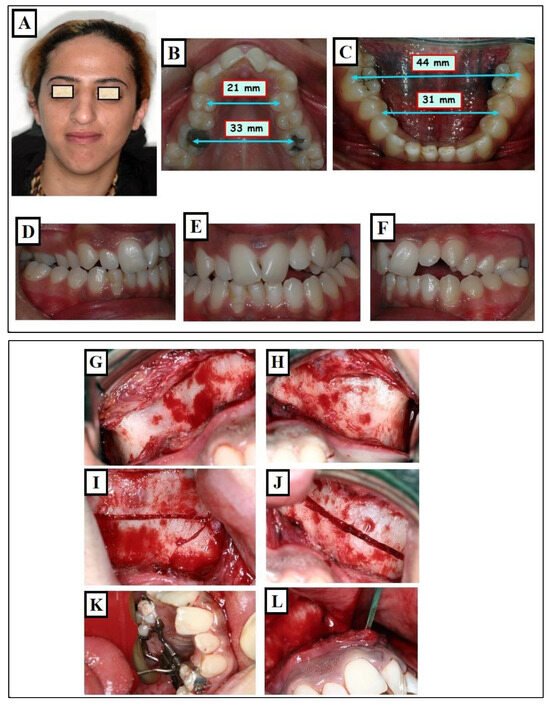

A prevalent therapeutic approach for younger individuals to address maxillary transverse deficiency is Rapid Maxillary Expansion (RME). The objective of this intervention is to broaden the midpalatal suture by exerting lateral forces against the teeth and marginal alveolar bone. RME proves effective in children and adolescents before sutural closure. However, in non-growing adolescents and young adults, the success rate of maxillary expansion decreases with the closure of sutures. (Figure 18A–L).

Figure 18.

Orthodontic expansion through a conventional RPE (Rapid Palatal Expander). Before treatment, a narrow face and mouth (A), narrow upper jaw (B), the width of the maxilla as seen from the midpalatal suture (white arrow) is symmetrical and narrow (arrows B) compared to the width of the mandible (arrows A), (C), and crossbite (D). The lower jaw has adapted to the upper jaw (E). An RPE was used for expansion (F). (G–L) describe the status after treatment. After the expansion of the maxilla, there was a harmonization of both jaw widths (arrows A, B) (I).

Expansion of the maxilla through Surgically Assisted Rapid Palatal Expansion (SARPE). Situation before treatment: narrow face and narrow nose (A), extremely narrow upper jaw (blue arrows 21mm, 33 mm) (B) compared to the lower jaw (blue arrows 31mm, 43 mm) (C), skeletal and dentoalveolar crossbite on the right and left (D–F). Surgical assistance for maxillary expansion. Surgical separation of the bones on the maxilla was partially performed at the level of Lefort I (G–L). Maxillary expansion with the screw (M,N). Cone-beam computed tomography (CBCT) after expansion shows the separation of Maxillary parts, as part of an examination, the amount of expansion at the bone was measured compared to the screw opening (O) and the airway the colored area represents the measured airways before and after expansion (P). Improvement in breathing and breathing disorders is expected in such patients. Condition after treatment, changes in facial width (Q), changes in jaw widths (R,S) with occlusion correction (T–V).